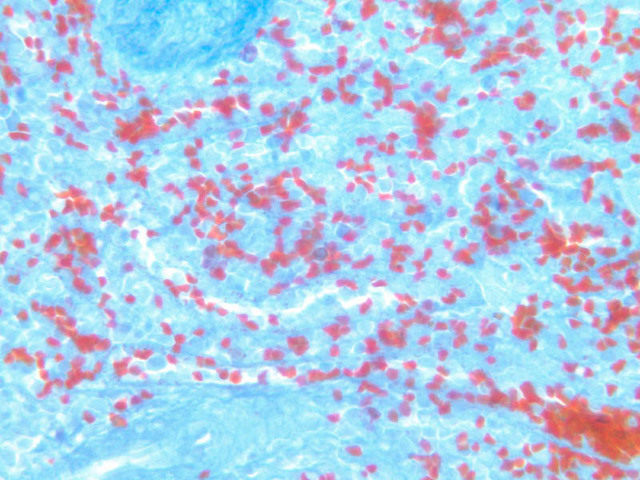

The remainder of the cellular mass in the spleen is red pulp (A-38 [10x, 20x, 40x]), made up of red and white cells of the blood enmeshed in the reticular tissue of splenic cords and present in the splenic sinuses. After passing through the PALS, the trabecular arteries branch to form smaller arterial vessels known as penicillar arterioles which narrow, forming arterial capillaries that empty into the cords of the red pulp (open circulation) or into the venous sinuses (closed circulation). In the splenic sinuses the cells of the blood are exposed to red pulp macrophages. The splenic sinuses eventually become confluent to form veins that enter the trabeculae and gradually merge meeting in the hilus to form splenic veins.

Examine the composition of the red pulp tissue. The three dimensional structure of the red pulp is analogous to Swiss cheese with the holes being the venous sinuses and the cheese being the parenchyma (i.e. splenic cords). On slide A-36 which is stained with Mallory's aniline blue locate examples of the splenic sinuses ([2.5x, 10x, 20x, 40x-labeled] [10x, 20x, 40x]). The walls of the splenic sinuses consist of adjoining specialized endothelial cells whose nuclei in many cases stand out from the wall in a bead-like fashion. The basement membrane of the epithelial cells stains blue revealing the sinuses quite nicely. Usually the sinus lumen is filled with red cells and leukocytes. The skeletal framework of the cords is provided by a network of reticular fibers. As above, the reticular cells are best seen using a reticular fiber stain (slide A-37 [2.5x, 10x, 20x, 40x-labeled]). Look for the large pale nuclei of reticular cells that have darkly stained reticular fibers. Fibers run irregularly in the cords, but clearly outline the sinuses around which they are wrapped. Notice on this same slide that there is much less reticular tissue in the white pulp than the red. The splenic cords occur around the sinuses and are distinguished by the presence of disintegrating red blood cells undergoing phagocytosis.

Here's a little histopathology: Observe slide A-40 (H&E [2.5x, 10x, 20x, 40x]). In this slide the corpses of red blood cells appear brown and can be seen littered throughout. These residual RBCs are referred to as hemosiderin. Slide A-39 (H&E [2.5x, 10x, 20x, 40x]) was prepared from a patient undergoing chemotherapy. How does the white pulp in this slide differ from the normal spleen, slide A-38?